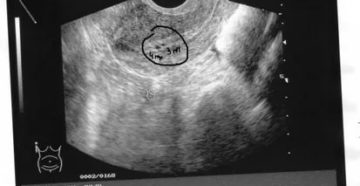

Желтое тело и его исследование методом УЗИ Чем больше о болезнях узнавали люди, тем более…